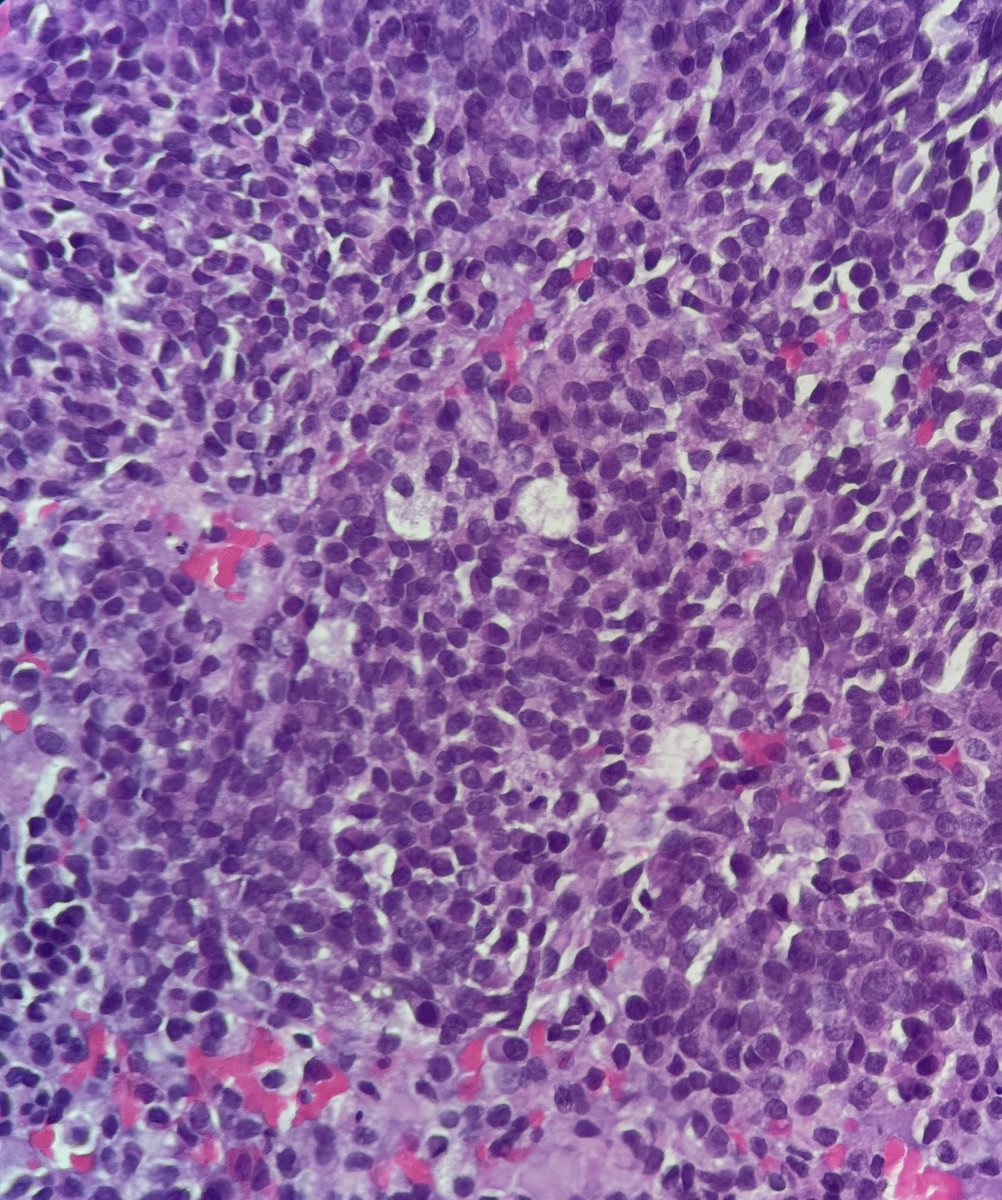

59-year-old woman with a destructive sinonasal tumor. Liver and iliac mets on CT. Biopsy performed (more pics below). Diagnostic opinions are welcome! #pathology #PathTwitter #surgicalpath #oralpath #entpath